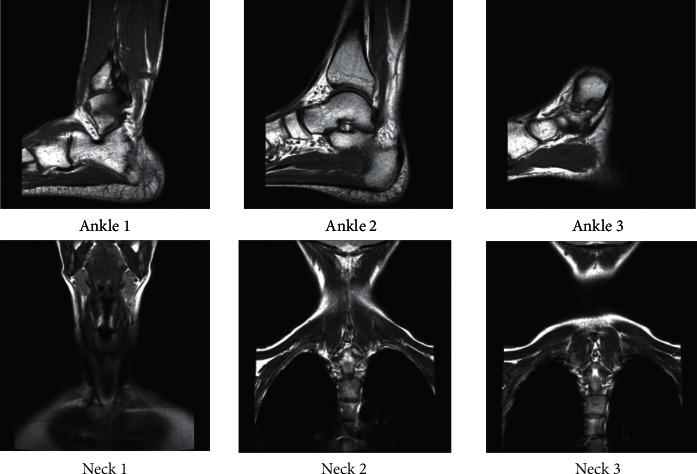

Magnetic resonance image has important application value in disease diagnosis. Due to the particularity of its imaging mechanism, the resolution of hardware imaging needs to be improved by increasing radiation intensity and radiation time. Excess radiation can cause the body to overheat and, in severe cases, inactivate the protein. This problem is expected to be solved by the image superresolution method based on joint dictionary learning, which has good superresolution performance. In the process of dictionary learning, the loss function will directly affect the dictionary performance. The general method only uses the cascade error as the optimization function in dictionary training, and the method does not consider the individual reconstruction error of high- and low-resolution image dictionary. In order to solve the above problem, In this paper, the loss function of dictionary learning is optimized. While ensuring that the coefficients are sufficiently sparse, the high- and low-resolution dictionaries are trained separately to reduce the error generated by the joint high- and low-resolution dictionary block pair and increase the high-resolution reconstruction error. Experiments on neck and ankle MR images show that the proposed algorithm has better superresolution reconstruction performance on ×2 and ×4 compared with bicubic interpolation, nearest neighbor, and original dictionary learning algorithms.

磁共振成像是疾病诊断中的重要应用。由于其成像机制的特殊性,硬件成像的分辨率需要通过增加辐射强度和辐射时间来提高。过量的辐射会导致身体过热,在严重的情况下会使蛋白质失活。基于联合字典学习的图像超分辨率方法有望解决这个问题,该方法具有良好的超分辨率性能。在字典学习过程中,损失函数将直接影响字典的性能。一般的方法只在字典训练中使用级联误差作为优化函数,该方法没有考虑高低分辨率图像字典的个体重建误差。为了解决上述问题,本文对字典学习的损失函数进行了优化。在确保系数足够稀疏的同时,分别训练高低分辨率字典,以减少联合高低分辨率字典块对产生的误差,并增加高分辨率的重建误差。对颈部和踝关节的磁共振图像的实验表明,与双线性内插、最近邻和原始字典学习算法相比,该算法在 2 倍和 4 倍的放大率下具有更好的超分辨率重建性能。